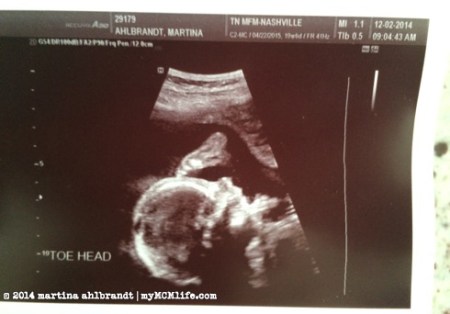

Look at that cutie! In the one below, baby’s toes were all the way up by his or her forehead. I love that she captioned it “TOE HEAD.”